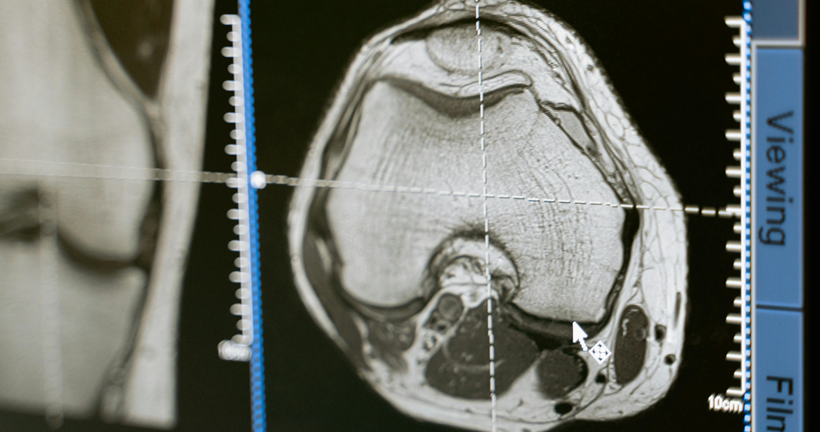

Resonancia magnetica y PET-FDG en la demencia frontotemporal variante conductual: revisión sistemática

Cristian SantiagoJácome Granda | Investigador La demencia frontotemporal (DFT) es una enfermedad neurodegenerativa compuesta por un conjunto de síntomas comportamentales y del lenguaje como consecuencia de la atrofia de áreas que pertenecen a lóbulo temporal y frontal. Según las características clínicas, la DFT se subdivide en tres variantes. La demencia frontotemporal variante semántica (DFTvnf) que se presenta con alteraciones en el lenguaje, principalmente en la capacidad de comprender y reconocer objetos. La demencia frontotemporal no fluente (DFTvnf) se manifiesta por una marcada disminución en la fluidez, fallo en la emisión de sonidos, así como agramatismo y la demencia frontotemporal variante conductual (DFTvnf) de la cual haremos énfasis en esta investigación, es una enfermedad neurodegenerativa poco estudiada y de inicio insidioso, que se caracteriza por la presencia de síntomas comportamentales y cognitivos que repercuten en el desenvolvimiento adecuado en las distintas actividades de la vida diaria. Dentro de la clínica presentada por pacientes que presente este tipo específico de variante se encuentra disfunción ejecutiva, apatía y desinhibición, además de la disminución en la empatía, alteraciones en los hábitos alimenticios y conductas estereotipadas marcadas, en ocasiones, se manifiesta mediante comportamientos compulsivos y conductas sexuales desinhibidas; los sujetos pueden presentarse agresivos, con una higiene personal desalineada, hiperoralidad, así como coprolalia. A pesar de que este cuadro es el más frecuente, existen perfiles caracterizados por la adinamia y la falta de iniciación. La presentación sintomatológica de la disfunción frontal dependerá de si la afectación predominante inmiscuye a regiones del cíngulo u orbitales. Además, las afectaciones de las funciones ejecutivas dependerán del daño en la corteza dorsolateral. Buscamos describir la relación existente entre la atrofia cerebral identificada en estudios de resonancia magnética estructural, PET-FDG y su implicación cognitiva sobre los pacientes con DFTvnf. La revisión sistemática se realizó bajo los criterios establecidos en la declaración PRISMA, considerando 80 estudios de las bases de datos Pubmed y ScienceDirect en donde por criterios de inclusión y exclusión la revisión final se realizó con 40 artículos de las bases de datos antes descritas. Como resultados en relación con los estudios analizados, se encontró que solo el 15% de artículos mantienen una correlación de áreas anatómicas - cognitivas, además se encontraron alteraciones en los dominios de atención, memoria y funciones ejecutivas mientras que los hallazgos de atrofia cerebral se localizan en áreas frontales, el cíngulo e ínsula. El diagnóstico de la DFTvnf es un proceso complejo que se compone de distintas etapas, por lo que, la presente revisión sistemática confirma la importancia de estudio de las manifestaciones clínicas, la evaluación neuropsicológica de procesos cognitivos y el papel de las técnicas de neuroimagen en la identificación de este tipo de variantes. Estos resultados contribuirán a obtener un diagnóstico oportuno y veraz de la DFTvnf, describir las manifestaciones clínicas de manera más específica además de beneficiar a los profesionales del área para la implementación de intervenciones adecuadas que permitan mejorar la calidad de vida de quienes la padecen. Leer el artículo completo

A PROPÓSITO DE UN CASO DE DEMENCIA FRONTOTEMPORAL – VARIANTE CONDUCTUAL CON SÍNTOMAS AMNÉSICOS E IMÁGENES CEREBRALES TIPO ALZHEIMER

LIZARDO CRUZADO | FACULTAD DE MEDICINA. UNIVERSIDAD PERUANA CAYETANO HEREDIA. LIMA, PERÚ. INSTITUTO NACIONAL DE SALUD MENTAL “HONORIO DELGADO – HIDEYO NOGUCHI”. LIMA, PERÚ La demencia frontotemporal (DFT) es un conjunto de trastornos neurodegenerativos de inicio temprano y gran heterogeneidad, tanto en su cuadro clínico como su etiología y hallazgos histopatológicos e imagenológicos. La DFT es la segunda causa más frecuente de demencia después de la enfermedad de Alzheimer (EA) en menores de 65 años, por lo que tiene un importante impacto en personas de edad productiva. La DFT se manifiesta clínicamente en dos grandes síndromes: DFT variante conductual (DFTvc), con alteraciones predominantes del comportamiento social y del control ejecutivo; y la denominada Afasia Progresiva Primaria, con los subtipos: afasia progresiva no fluente, demencia semántica y afasia logopénica, donde el lenguaje es más afectado. La DFTvc representa entre el 50 a 60% de casos de la DFT y predomina en varones respecto a mujeres (2 a 1). En el cuadro clínico, la pérdida de empatía con los demás se combina con la desinhibición, la apatía, el aplanamiento emocional y la indiferencia afectiva. Muchas veces se confunde a la DFT con una serie de diagnósticos psiquiátricos (esquizofrenia de inicio tardío cuando aparecen síntomas psicóticos, manía por la desinhibición, depresión por la apatía, trastorno obsesivo compulsivo por las estereotipias), asimismo, la DFTvc en sus etapas tempranas puede originar cuadros secundarios de ludopatía, compras compulsivas, coleccionismo patológico, adicciones y otras patologías psiquiátricas. Estudios recientes hallan hasta en 15% de casos de DFT-vc, déficits en la memoria episódica similar a los de la EA, incluso desde estadios tempranos. Asimismo, los estudios imagenológicos han hallado afectación de regiones hipocampales y temporales en estos casos de DFT-VC, similares a las que se aprecian en casos de EA. Esto contradice el paradigma diagnóstico en que la memoria no sufría alteraciones con la DFT-vc. Asimismo, existen interesantes aportes desde la orilla de las investigaciones sobre enfermedad de Alzheimer con variantes conductuales – disejecutivas y conductuales, es decir, enfermedad de Alzheimer pero con síntomas más bien típicos de la DFTvc: como si hubiera un muy amplio espectro cuyos extremos son la EA y la DFT típicas pero que abarcan cuadros intermedios. A propósito de un caso ilustrativo hacemos una revisión breve de la bibliografía. Pulse para leer el artículo completo